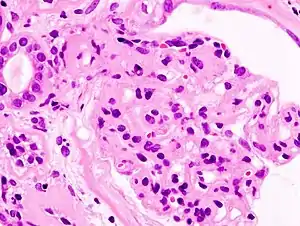

Microscopic image of diabetic glomerulosclerosis, the main cause of nephrotic syndrome in adults.

Diabetic glomerulonephritis in a person with nephrotic syndrome.

Secondary causes of nephrotic syndrome have the same histologic patterns as the primary causes, though they may exhibit some difference suggesting a secondary cause, such as inclusion bodies.[21] They are usually described by the underlying cause.

• Diabetic nephropathy: is a complication that occurs in some diabetics. Excess blood sugar accumulates in the kidney causing them to become inflamed and unable to carry out their normal function. This leads to the leakage of proteins into the urine.